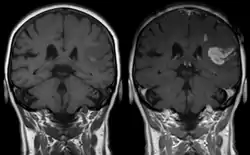

![]() تصوير بالرنين المغناطيسي لسكتة دماغية إفقارية (اليسرى بالصبغة، واليمنى بدون صبغة) تصوير بالرنين المغناطيسي لسكتة دماغية إفقارية (اليسرى بالصبغة، واليمنى بدون صبغة) | |

يُستخدم التصوير المقطعي المحوسب والتصوير بالرنين المغناطيسي لتشخيص سكتة منطقة المهطل، ومن ثَم يتوفر عدد من خيارات العلاج، منها علاج التصلب العصيديوتوسيع الأوعية الدموية المسدودة، بجانب العلاج التأهيلي والوقاية المستقبلية من السكتات الدماغية.

يبدأ تشخيص السكتات بشكل عام بإجراء فحص عصبي عام يساعد على تحديد المنطقة المصابة، يليه إجراء تصوير مقطعي محوسب للدماغ لاستبعاد وجود أي نزيف دماغي. لاحقا يمكن إجراء التصوير بالرنين المغناطيسي (باستخدام تتابع خاص)، ويعتبر الرنين المغناطيسي شديد الحساسية في تحديد المنطقة المصابة.